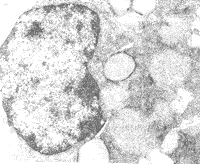

(二)气道及其周围肺组织病理学观察结果:吸入OA 0.5 h后光镜下可见哮喘组豚鼠支气管及其周围组织PMN浸润,嗜酸细胞增多。粘膜基底膜形态不规则,支气管管腔缩小,平滑肌层增厚(见图1)。透射电镜下见气道上皮细胞肿胀,胞浆内内质网增多,线粒体肿胀,呈细胞增殖倾向(见图2)。

Fig 2 Airway epithelial cell endoplasmic reticulum hyperplasia, mitochondrial swelling in asthmatic guinea pig ×200

图2 哮喘组气道上皮细胞粗面内质网增多,呈“池”状扩张,线粒体肿胀